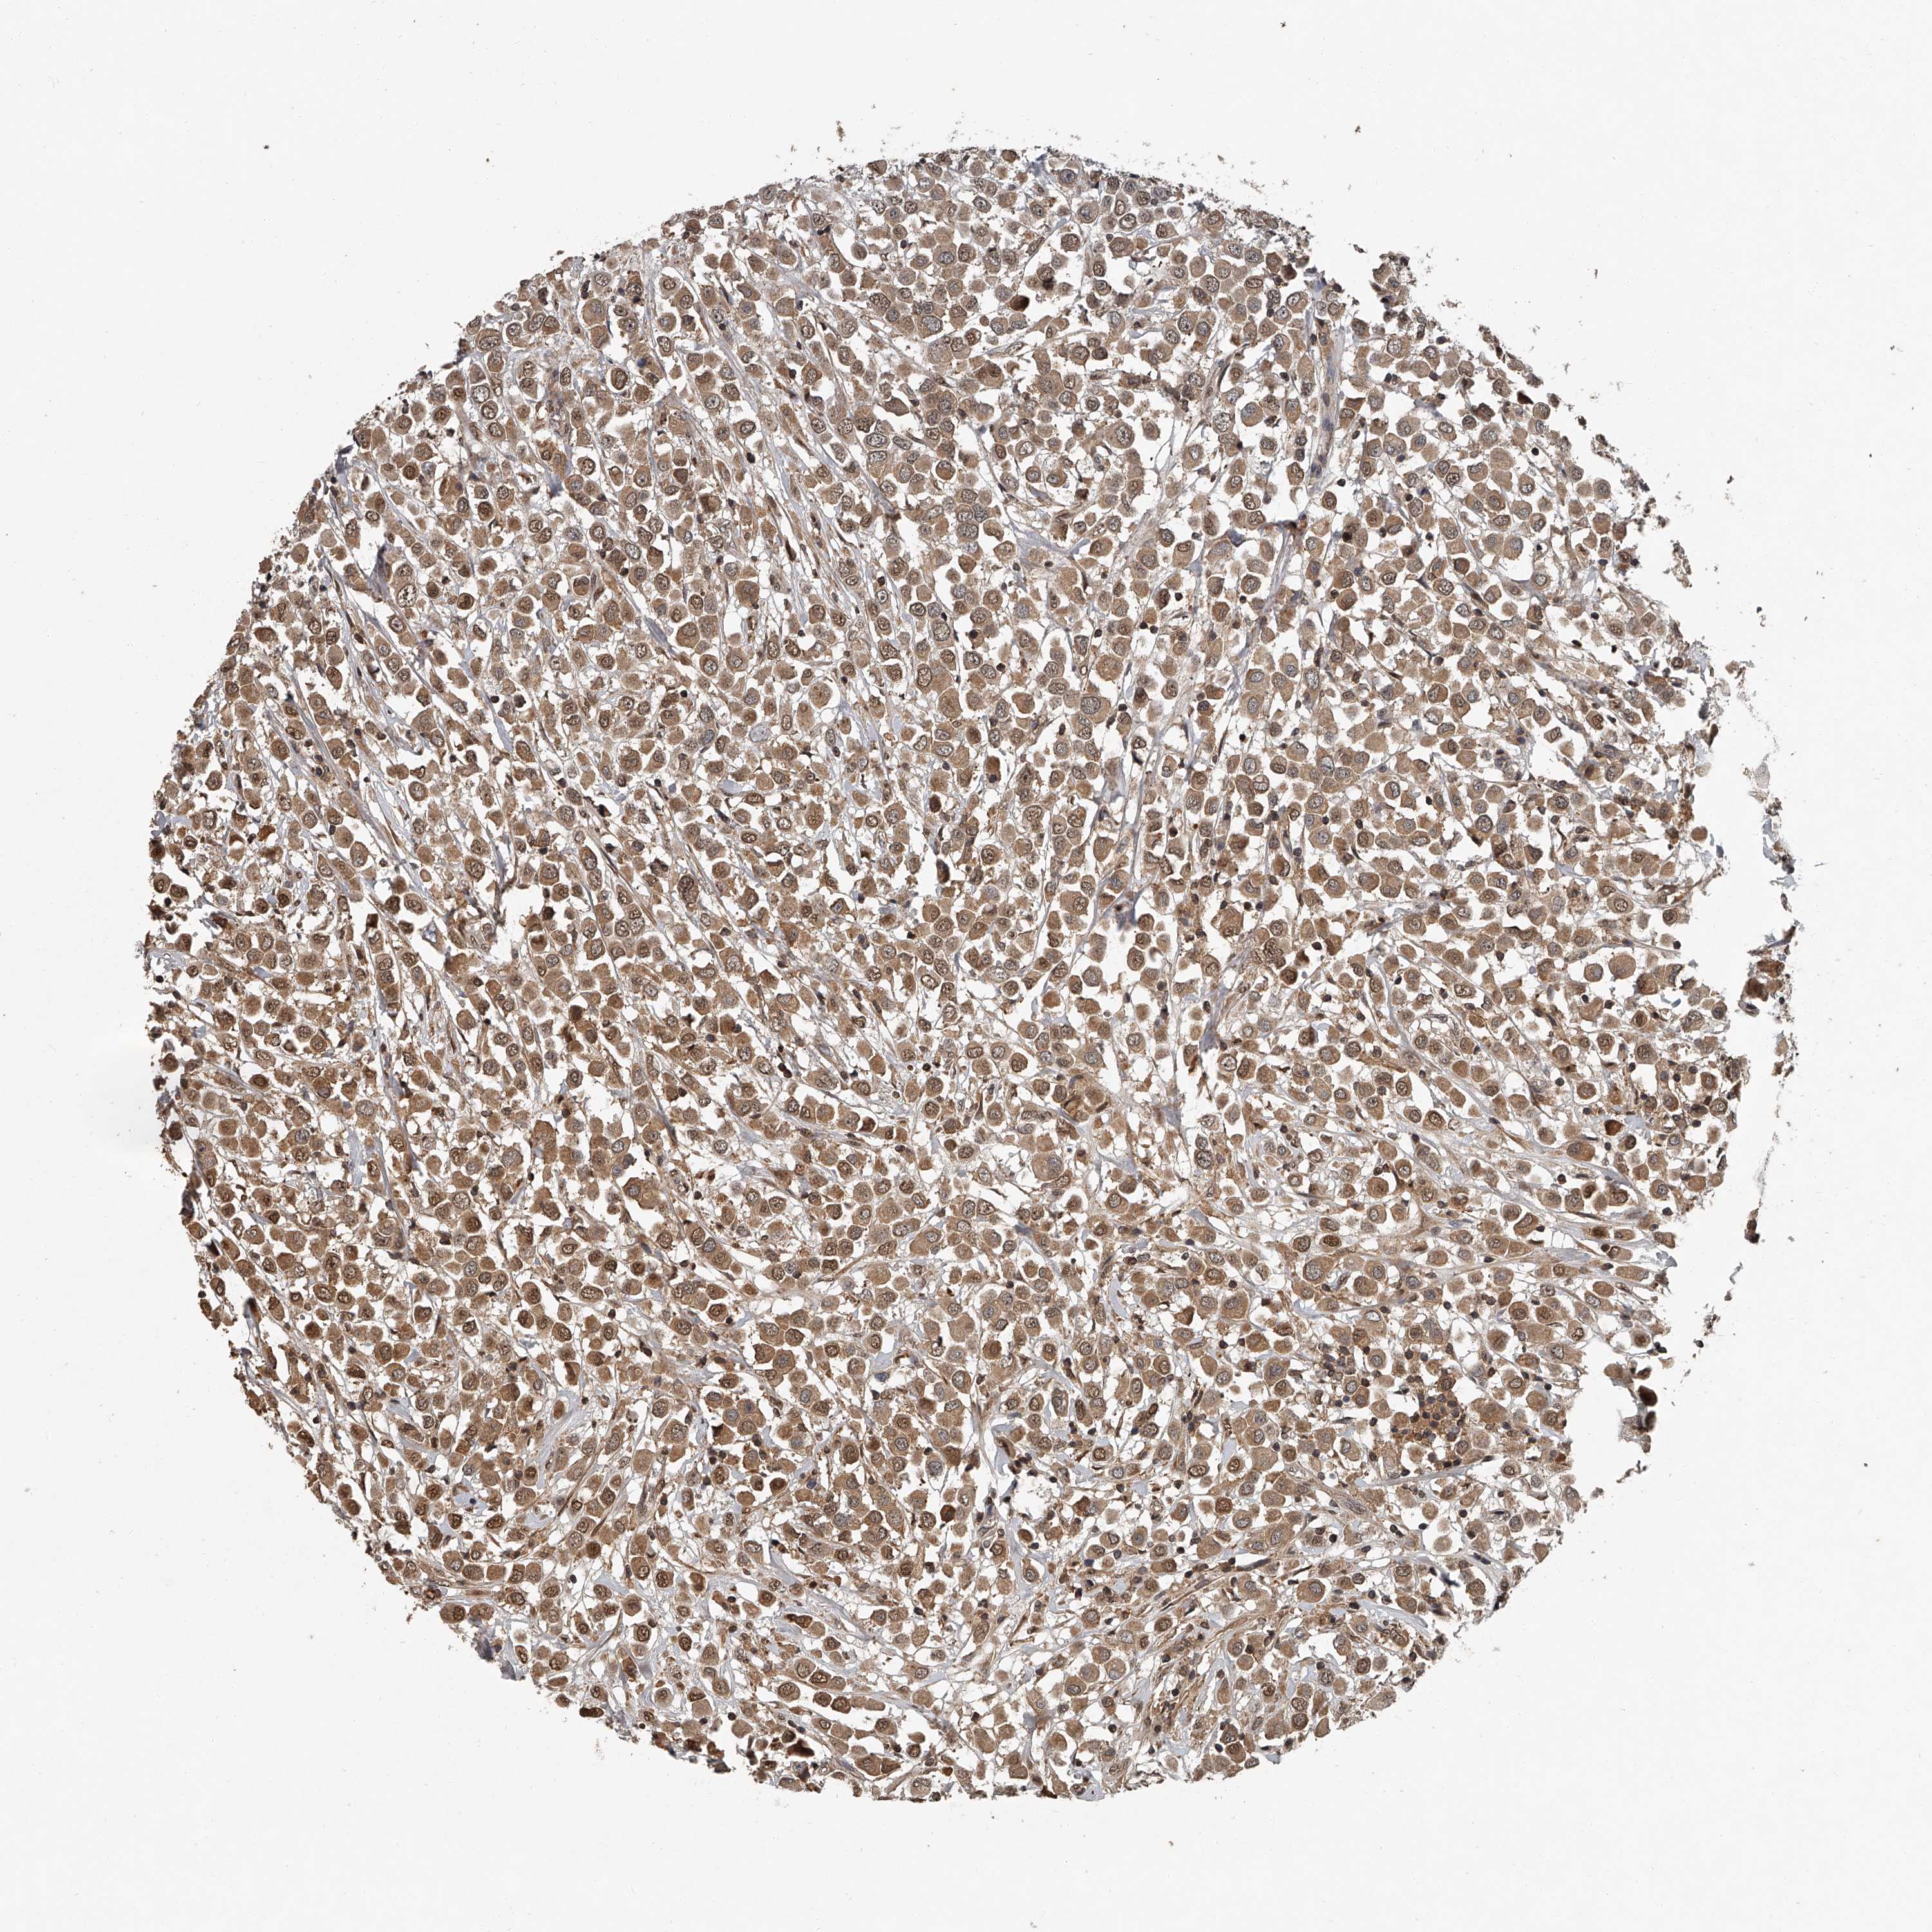

BRCA TCGA BRCA VALIDATION PROTEIN EXPRESSION